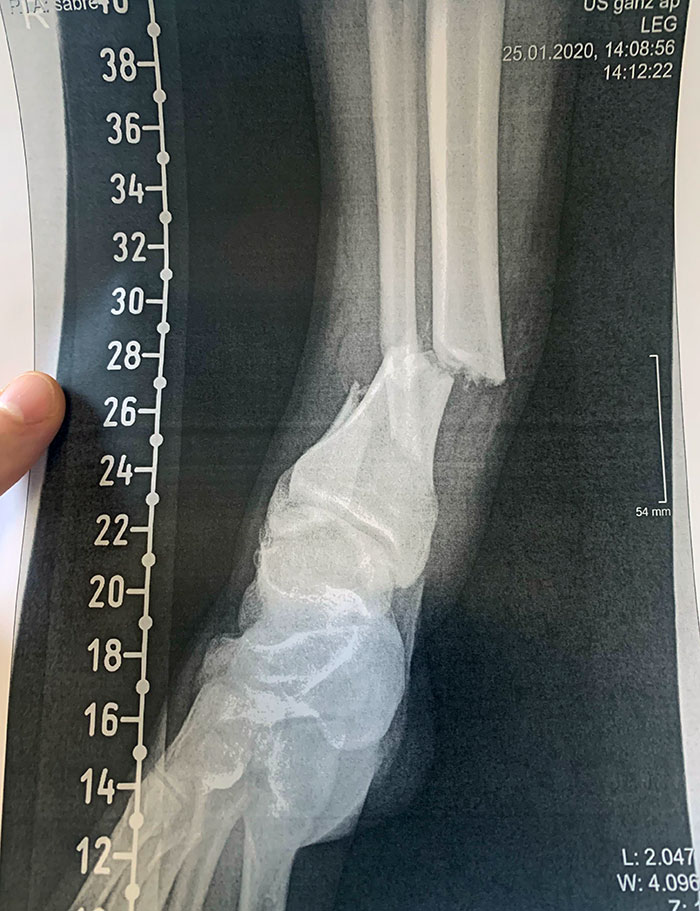

Pisé una pieza de lego y me rompí el tobillo